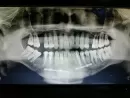

У меня был двойной перелом нижней челюсти. Сделали операцию не правильно, сделали заново операцию, но уже другой хирург. В этот раз, сделали все правильно, как показывает рентген. Сделали операцию 2 месяца назад, сделал снимок, левая часть костей срослась, а правая между зубами 43-м и 45-м не срослась полностью. Я не знаю зубы, десна или челюсть двигается, когда языком дотрагиваюсь.

Это может быть связано с тем, что трещина большая и костная мозоль не сформировалась.